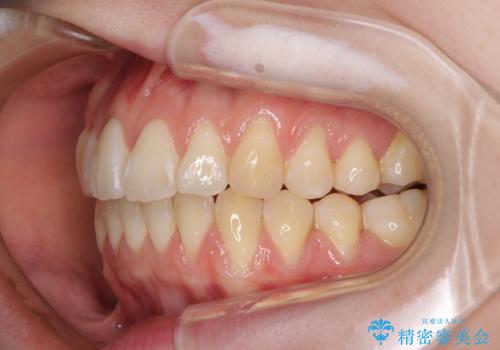

気になるデコボコとオープンバイト インビザラインでの矯正治療

- 前歯のデコボコと上下が開いていることを気にして来院された患者様です。

いわゆるオープンバイトは、インビザラインによる治療が適しているため、インビザラインにて治療を行うこととしました。

オープンバイトは容易に後戻りを起こすため、少しでも後戻りリスクを軽減するために舌癖改善のトレーニングをしっかりと行っていただきました。